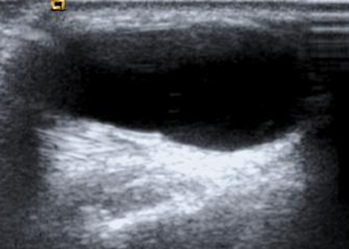

Se identifica en la ecografía como una masa uni o multilocular, anecoica, con reforzamiento posterior y que no comprime. (Fig 106).

Fig 106. Ganglión quístico.

Ecografía sagital. Lesión de consistencia líquida en el dorso de la muñeca, por ganglión quístico.